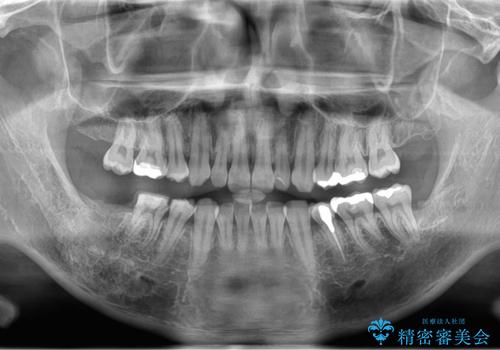

- 銀歯を白くしたいとのことで来院。

右下の被せ物を外し虫歯を除去したところ虫歯が深く保存が難しい状態だったので抜歯を行いました。

手前の銀の詰め物のところは除去して拡大鏡下で虫歯を取り除き、ジルコニアクラウンで治療を行いました。

抜歯したところは抜歯後骨の治癒を待ち、CTを撮影しインプラント治療ができる事(骨の厚みなど)確認し治療を行いました。